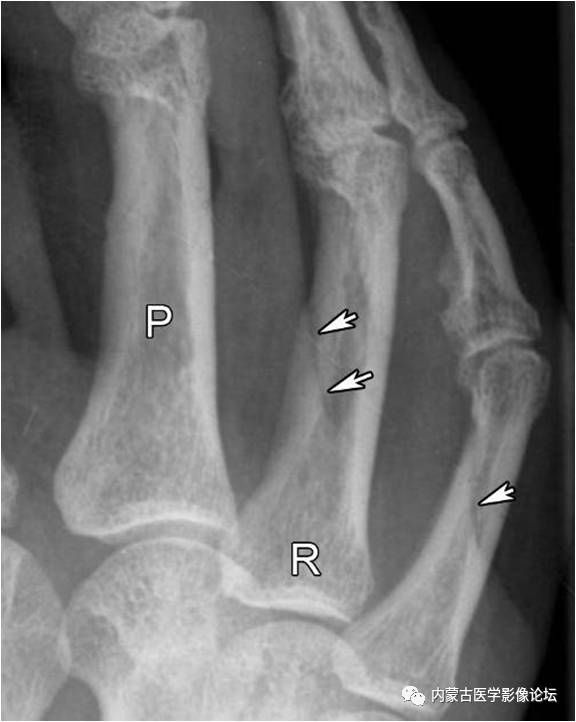

指骨滋养血管:箭头所示斜行透亮线影为近节指骨滋养血管,而白箭所示小圆形透亮区为中节指骨滋养血管轴位投照所致。注意指骨滋养血管从近端斜向远端,从骨皮质斜行走向髓腔,与掌骨相反。R:环指,P:近节指骨。